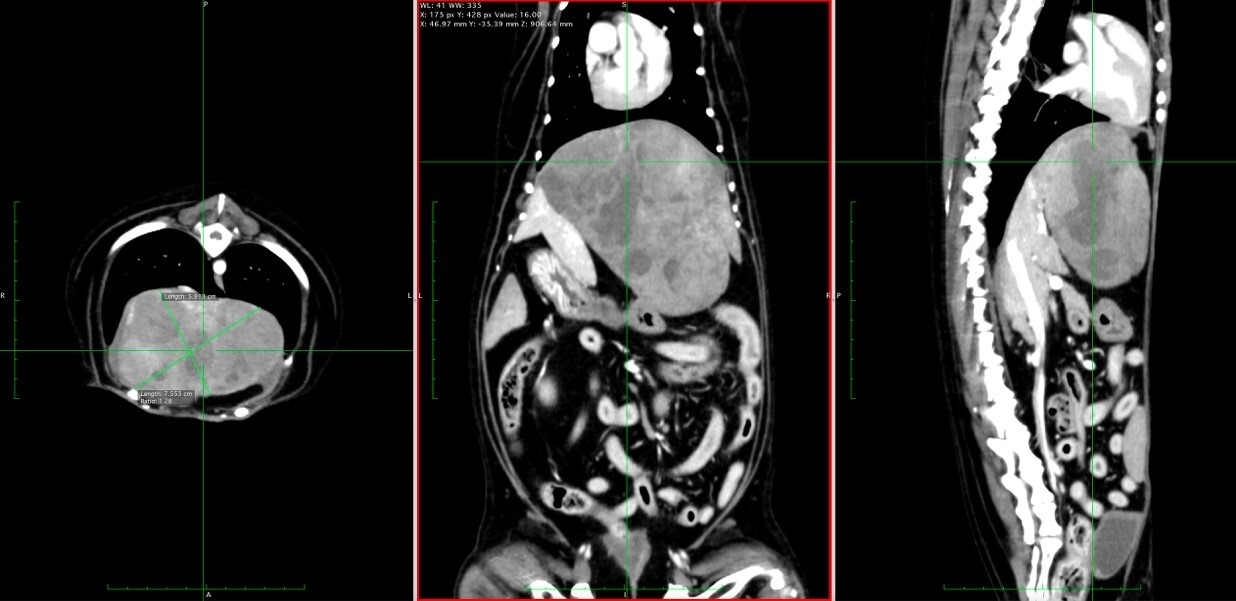

腫瘍の摘出手術を行います。腫瘍の浸潤の程度を確認するため、事前にCT検査を行う場合もあります。

CT検査にて観察された犬の肝細胞がん(青く着色された部分)